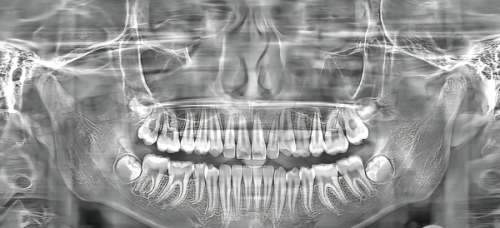

再给大家透个底:思南县人民医院的正畸方案是“个性化定制”的——医生会先用**数字化全景机**拍你的牙齿片,再用电脑模拟矫正后的成效,让你提前看到“整完牙的样子”,而且整个矫正过程都会有医生跟进,有问题随时找得到人,特别放心!